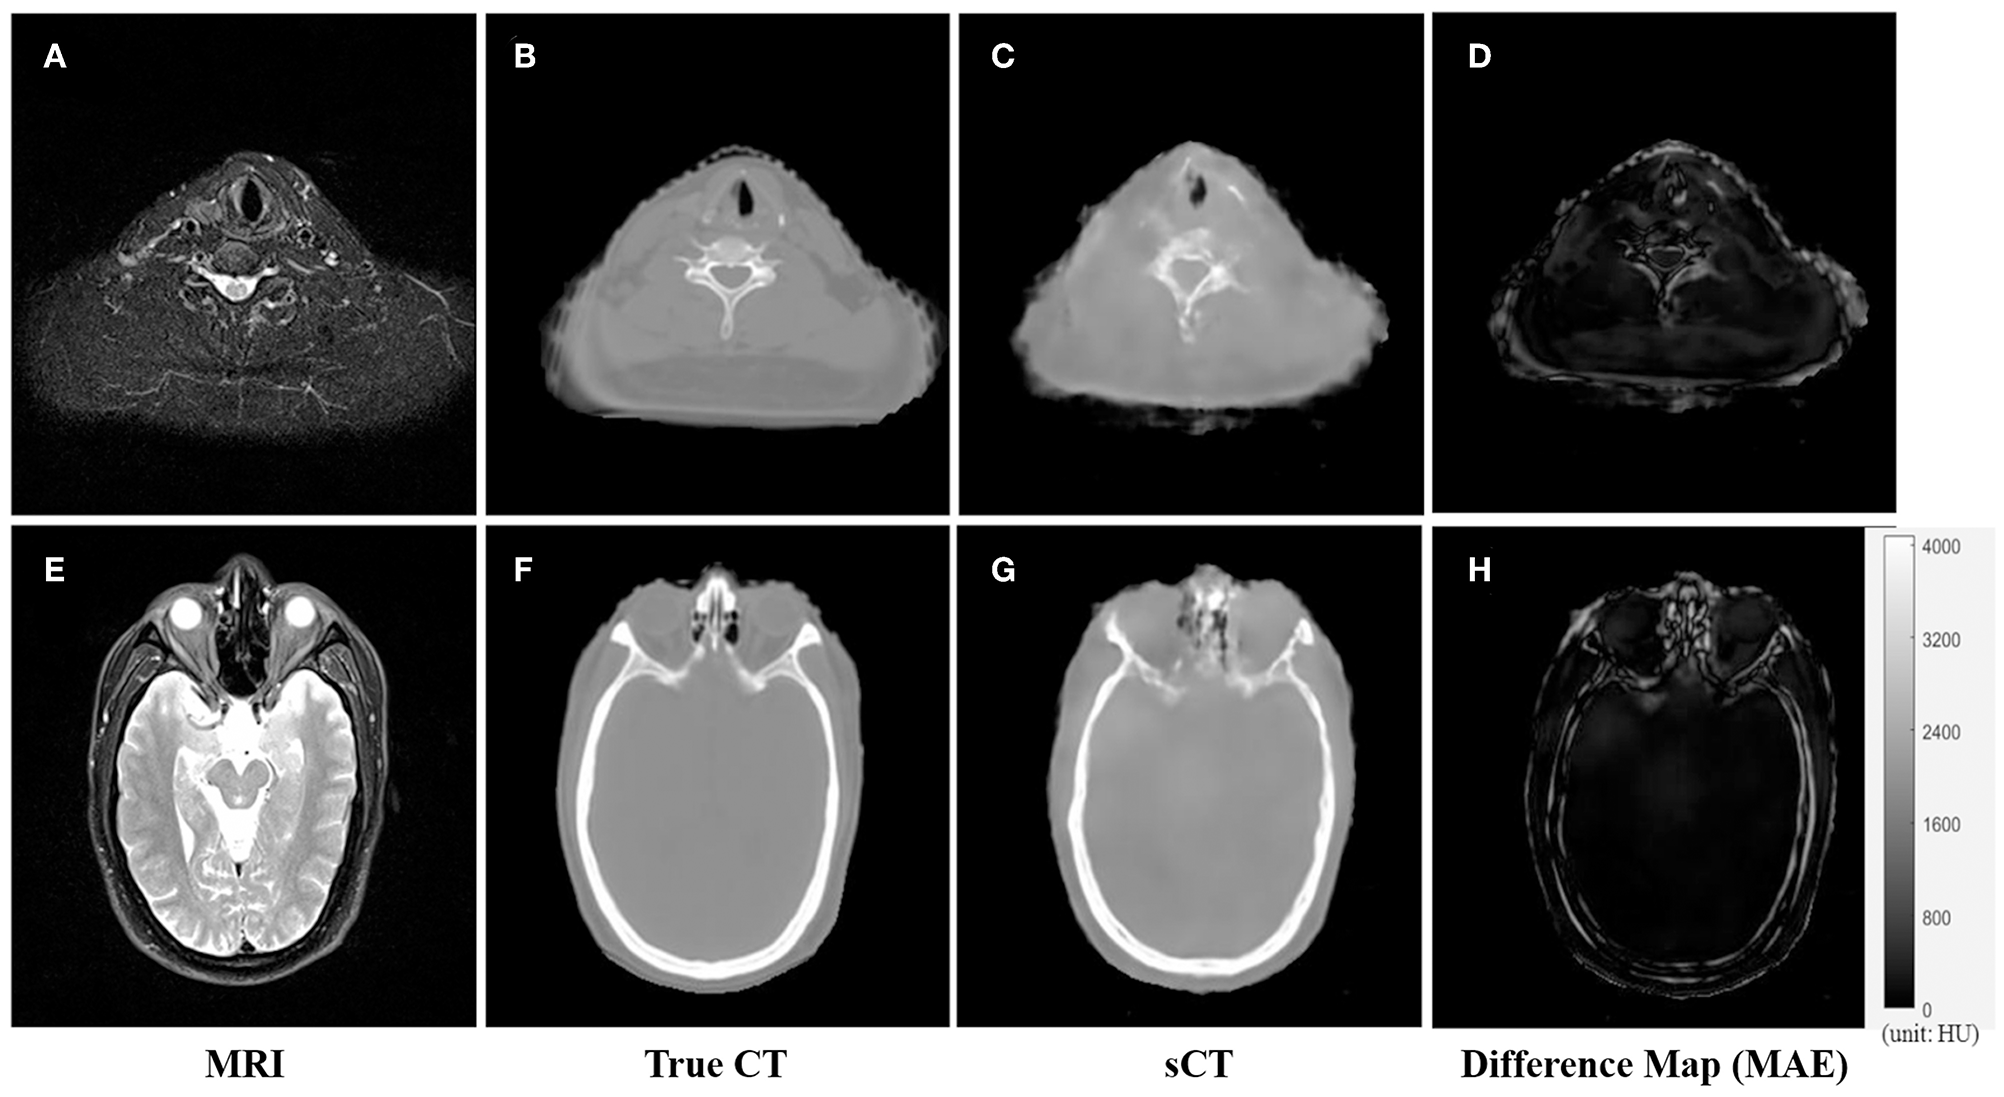

An example of the T2-weighted MRI, true CT-sim, synthetic CT, and MAE differences in the axial view of two representative slices was shown in the first to fourth column in Figure 3. Soft tissues in the synthetic CT (Figures 3C,G) had similar intensities as the true CT (Figures 3B,F). The major difference between true CTs and synthetic CTs was in the air-bone and bone-soft tissue interface (Figures 3D,H: the MAE map).

Figure 3. The comparison of CT and synthetic CT for two representative MR images. (A) MR image in the neck region; (B) real CT image aligned with (A); (C) synthetic sCT converted from MR image (A); (D) difference map between (B,C); (E) MR image in the head region; (F) real CT image; (G) synthetic sCT image; (H) difference map between (F,G). Gray bar in (H) indicated the mapping from CT number to gray scale in the difference maps.